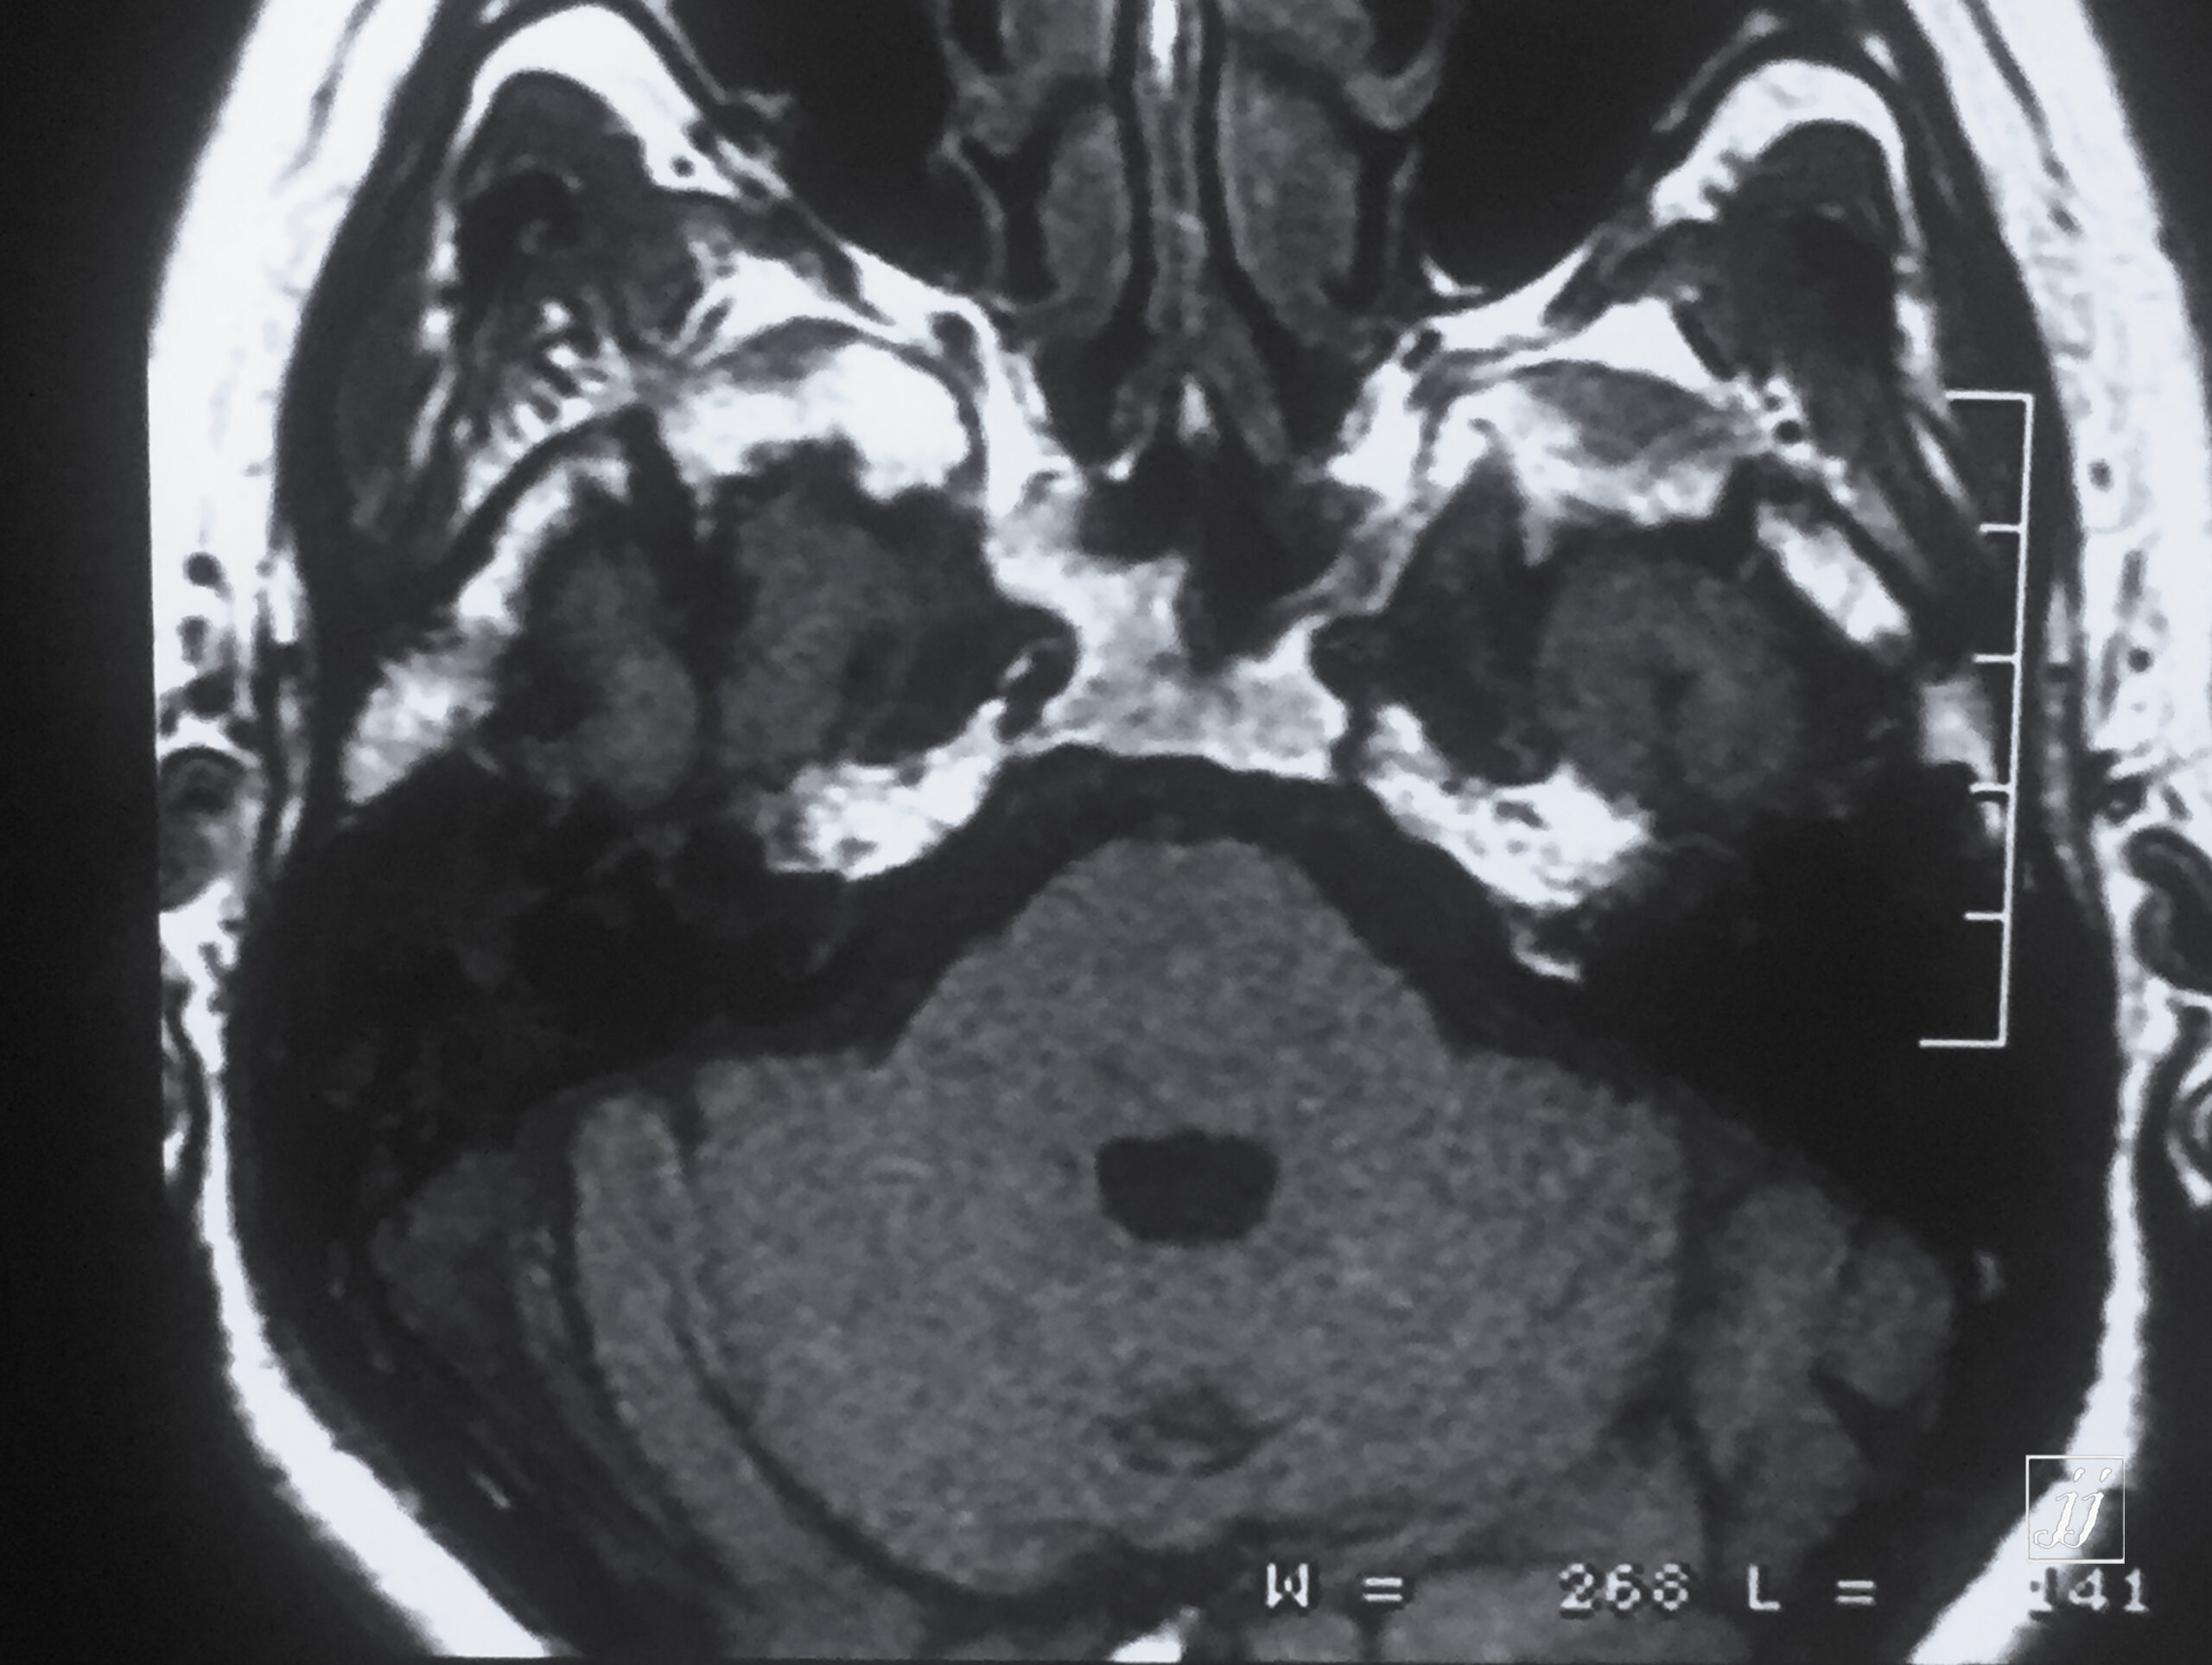

Brain- left glomus jugulars tumor (12)